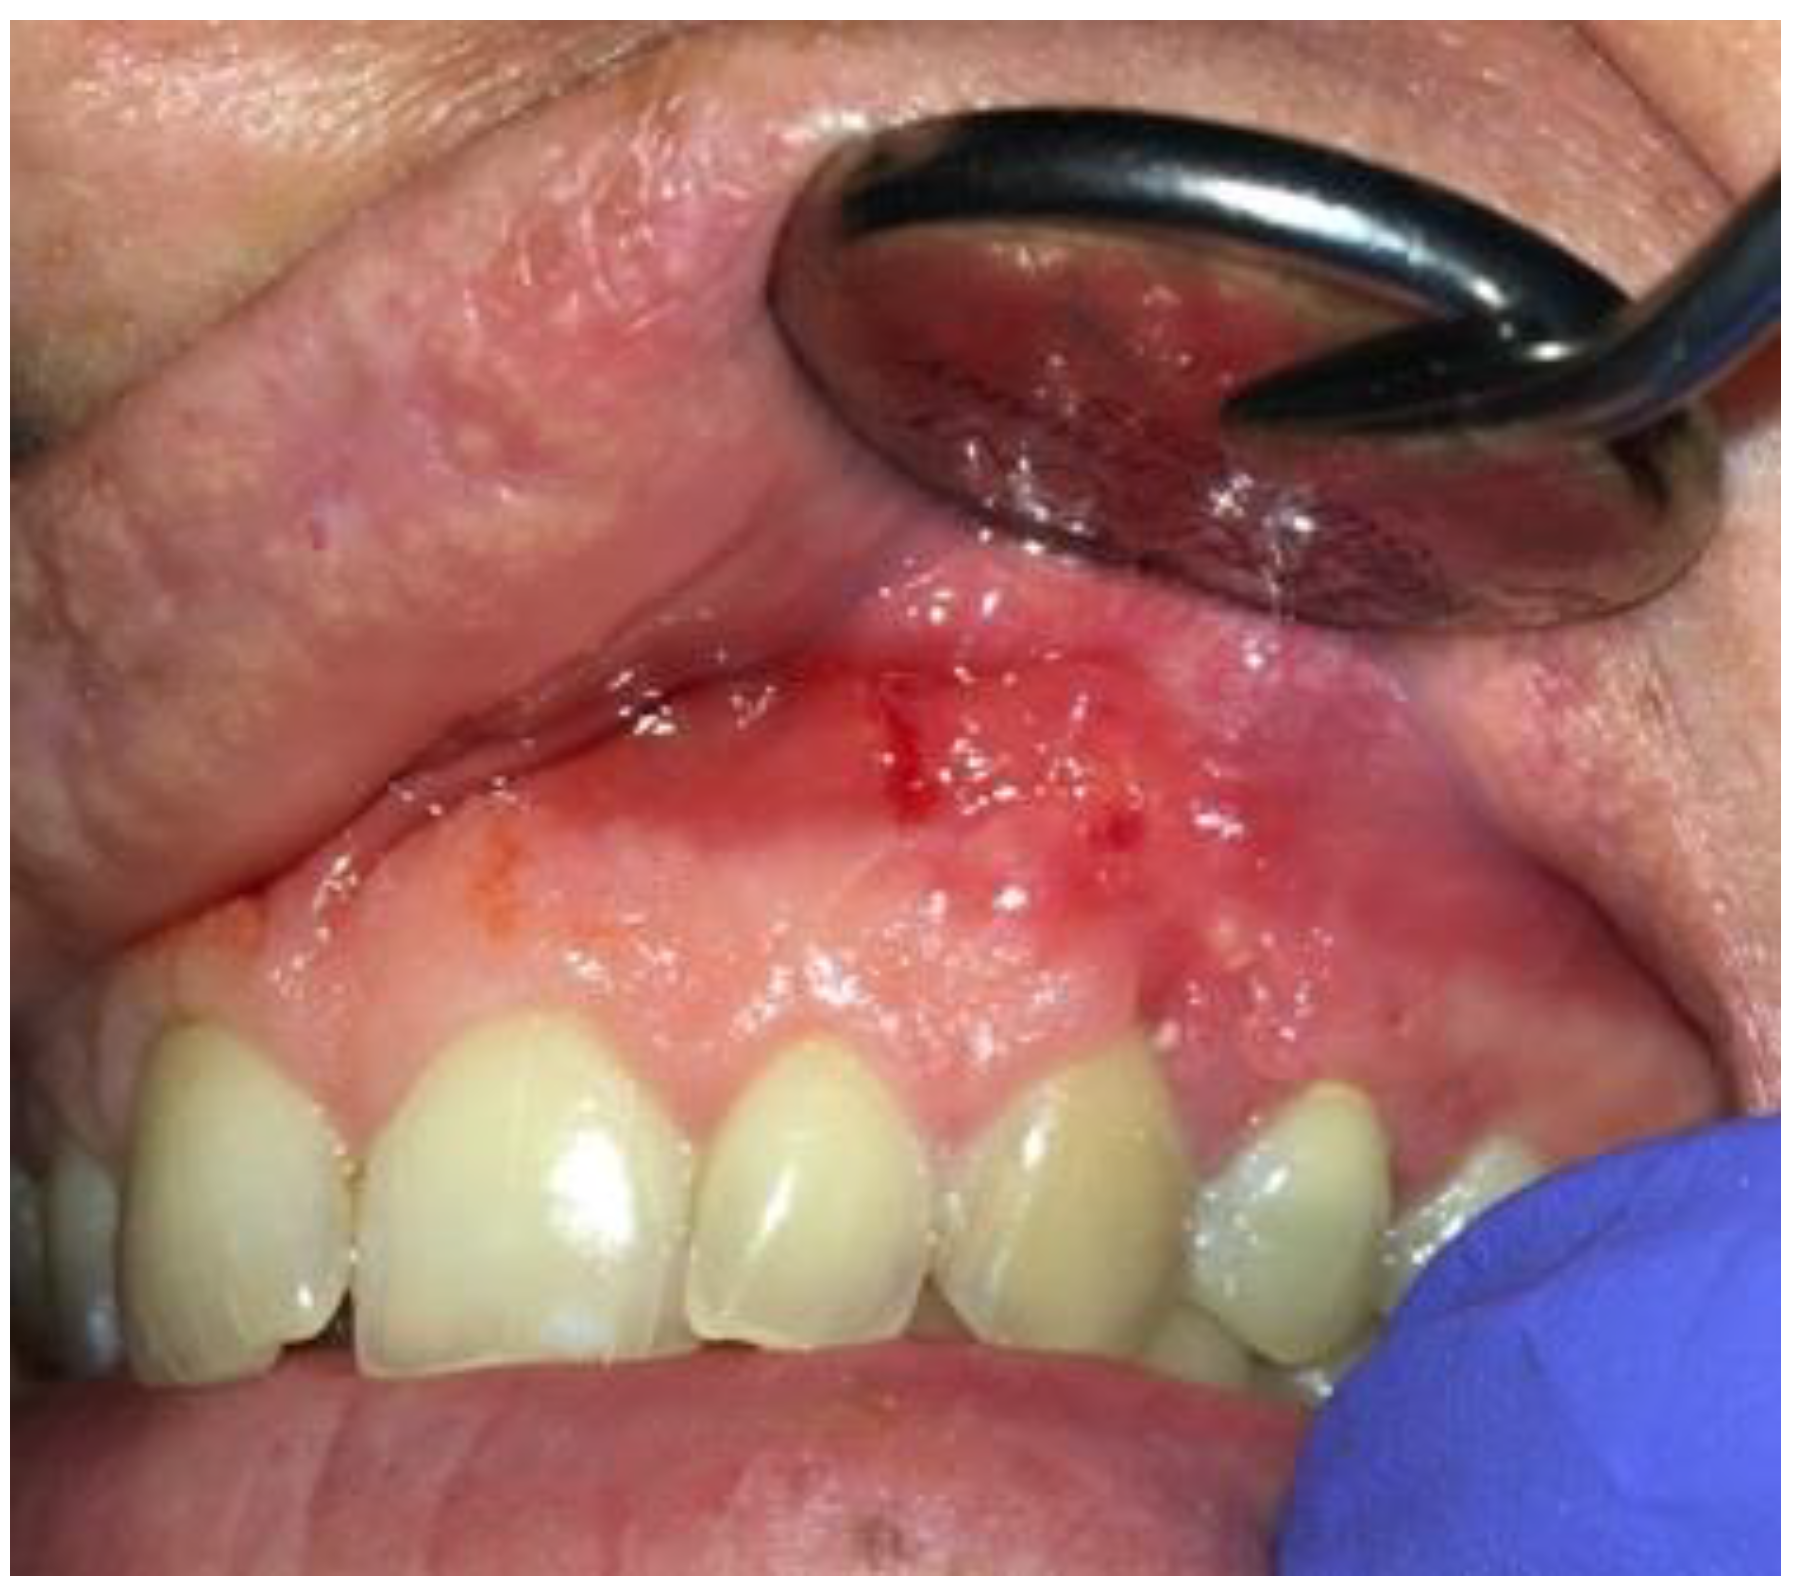

A 35-year-old female patient presented with a small, well-defined lesion on the attached gingival area, approximately 5/6 mm in diameter between roots of teeth 23–24, reported to the Privat Dental Clinic. The patient’s main concern was focused on gingival asymmetry and a tumor-like mass, painless and sometimes tender on tooth brushing. Clinical anamnesis revealed the occurrence of this asymptomatic mass for over 6 months. Because of swelling and atypical cortical expansion, the patient was referred for consultation and treatment. The patient was generally healthy without any chronic illness or important medical and dental past. A routine panoramic radiograph revealed a well-defined, radiolucent, left maxillary lesion located between the roots of the canine and first maxillary premolar (Figure 1 and Figure 2).

Clinically, teeth remain vital, non-displaced, stably situated in the alveolar socket with visible asymptomatic solitary swelling on the buccal gingiva with visible perforation of buccal cortical plate, not fluctuant on palpation. No ulceration or perforation through the attached gingiva was present. Presented cystic lesion was unilateral, painless in examination, and well related with adjacent expanded gingiva. Neither inflammation nor abscess formation was present. Both premolars responded well to cold stimulus. Surrounding teeth dental and periodontal status was good, all vital signs normal, and there was no periodontal disease without inflammated sockets or any other pathologies in surrounding bone and periodontal structures.

Figure 2. LPC expanding towards attached gingiva with buccal cortical plate resorption.